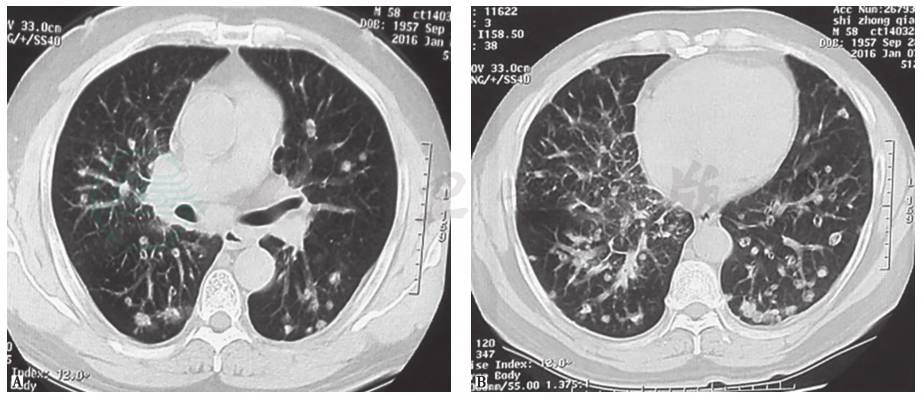

(1)肿瘤性病变

本例患者为老年女性,平时身体健康,无结构性肺病病史,入院前行肠镜检查提示乙状结肠溃疡性浸润性病变,且有明显体重下降表现,不能排除胃肠道肿瘤肺转移的可能。肺转移性肿瘤可分为血行性转移和淋巴性转移,以前者多见。经血行转移时可出现双肺结节样病灶,多为圆形或类圆形,边缘光整,密度均匀,以两中下肺多见(图3)。而本例患者胸部CT表现为不规则结节影,部分可见支气管充气征象,且短期进展迅速,考虑为肺转移性肿瘤可能性不大,但须进一步检查相应临床指标以排除之。

图3 肺转移性腺癌胸部CT表现

男性患者,58岁,咳嗽、咳痰3个月,气喘2个月,诊断为肺转移性腺癌。胸部CT见双肺多发结节性病变,部分空洞形成